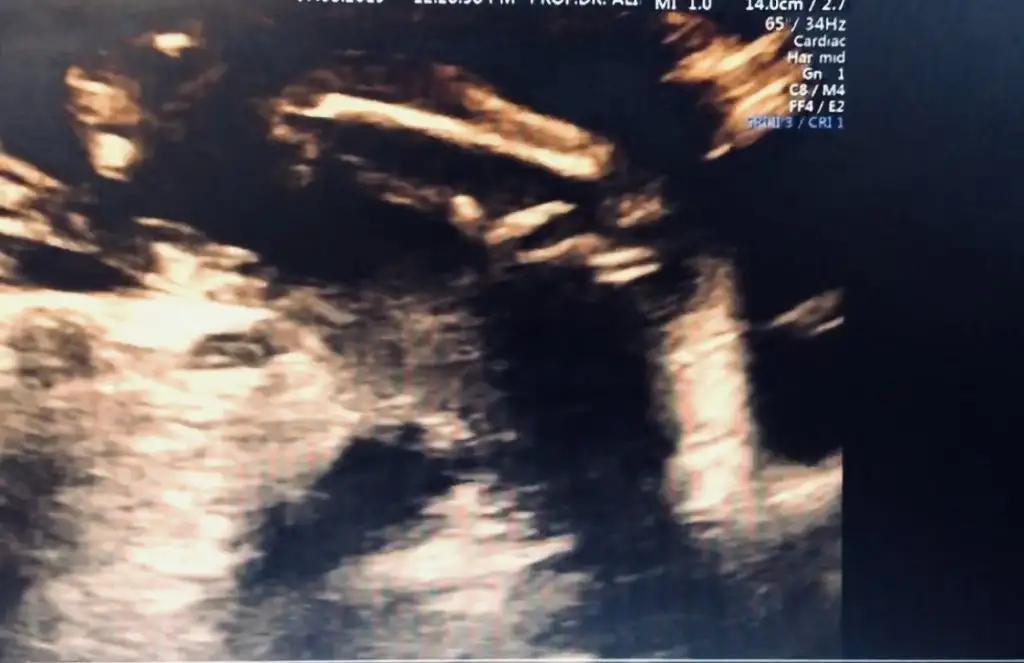

13+ haftasında nub olmaz bende kafa yapısına kız dedim saglıkla gelsin ogluşunBanada tahmin yapın kızlaaar![]()

Amin canım teşekkür ederim13+ haftasında nub olmaz bende kafa yapısına kız dedim saglıkla gelsin ogluşun![]()

Kız gibi